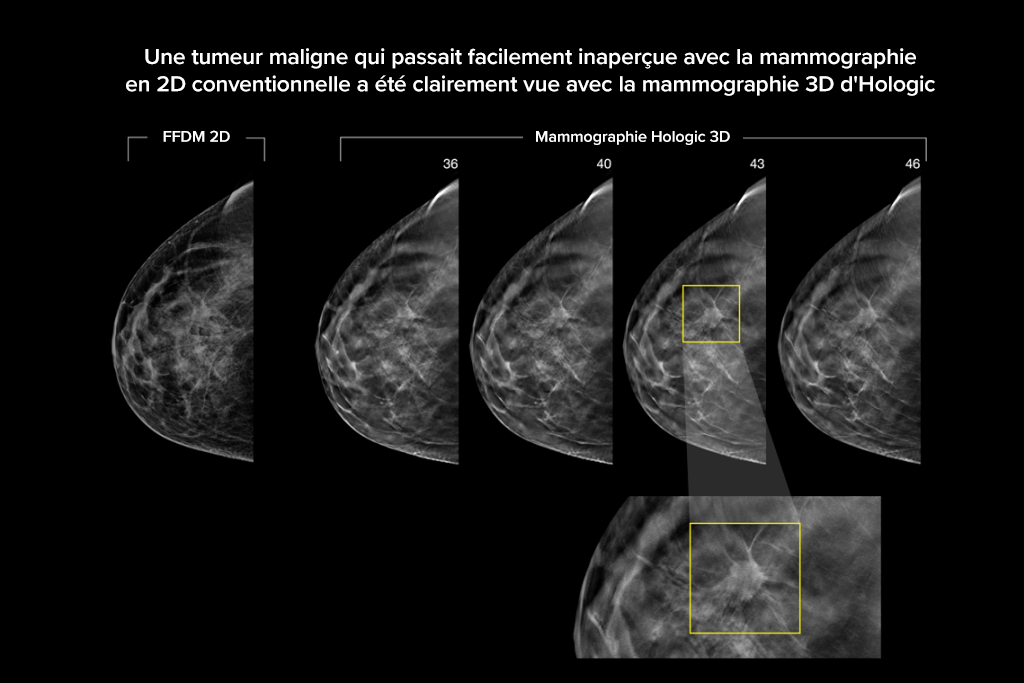

Le système Selenia Dimensions bénéficie de la précision prouvée de notre examen 3D Mammography pour détecter beaucoup plus tôt davantage de cancers invasifs du sein et diminuer les rappels par rapport à la 2D seule.2-6,*

Détectez jusqu’à 65 % de cancers invasifs en plus et réduisez les rappels de 40 % par rapport à la 2D seule.2-4,*

Une plus grande précision pour les femmes présentant des seins denses par rapport à la 2D seule.6